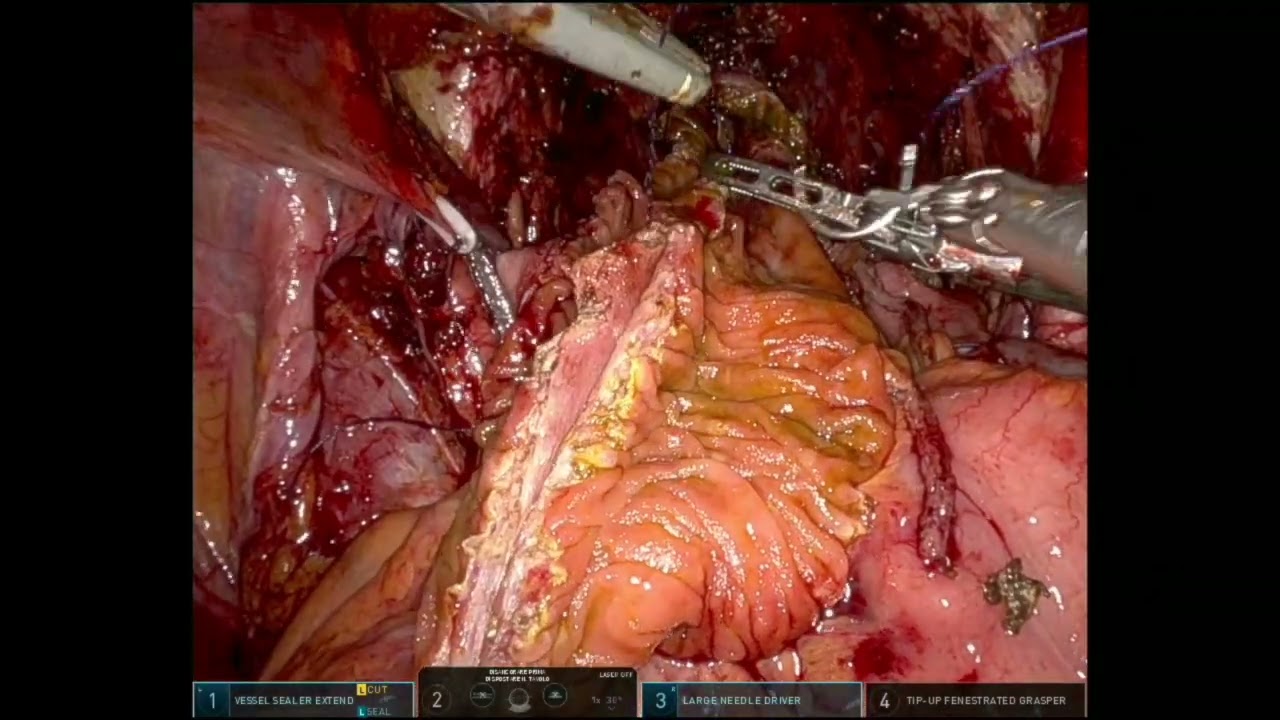

#178 Robotic Lateral Lymph Node Dissection Dr. Ankit Sharma, Dr. Avanish Saklani

KS Awards, Robotics, Surgeon ';